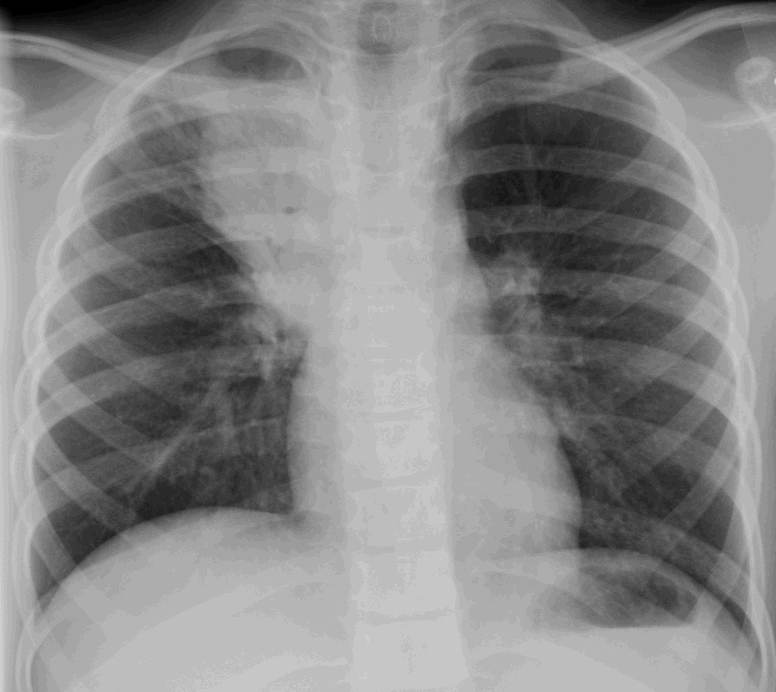

Community Acquired Pneumonia

It is certainly the season for pneumonias (even my little daughter had a significant one – see above)… and you will encounter community acquired pneumonia… so, let’s talk therapy.